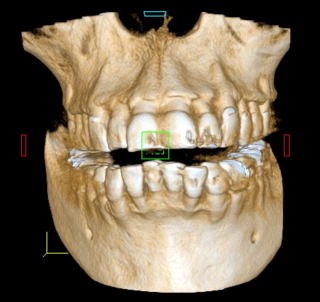

■Volume Rendering(CT)

当Clinicでは、すべてInterdisciplinary Treatment(包括的治療)を基本にしている。患者は38年間当Clinicで口腔管理をしている症例

である。開業当初から当診療システムで38年間口腔管理をしている。Panorama、CTなどレントゲンを介しての顎骨・歯槽骨の形態・骨

量などを観察したもので、歯槽骨の吸収状態から診ても、ほぼ二十歳代に相当するように思われる。過去の論文を見ても、口腔内写真

歯周病治療38年経過:83歳(女性)残存歯数28本